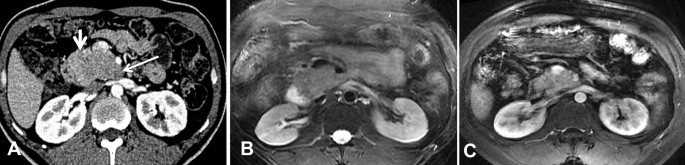

CT and MRI images of a 36-year-old man with pathologically confirmed PB. (A) In the AP view, the tumors presented as exogenous hypovascular masses in the head of the pancreas. The tumor exhibits an exophytic growth pattern, similar to branches growing outward from a tree trunk, and the long arrows indicate that the tumors have a tapering head. The short arrows indicate that the interface between the root of the tumors and the head of the pancreas is not clear. The MRI examination showed that the mass was isointense on T2WI (C).

CT image of a 37-year-old man with pathologically confirmed PB. (A) In the VP view, the mass appears as an isodense mass with well-defined cystic degeneration in the peripheral portion of the mass. (B) The sagittal MPR images show that the tumor exhibits an exophytic growth pattern, similar to branches growing outward from a tree trunk, with a pointed head deep into the hilum of the liver (arrow).

In our study, the average tumor dimension was 4.1 × 6.3 cm (range 2.3 × 4.3 to 7.3 × 12.4 cm). Tumors were located in the head of the pancreas in three patients (42.9%), in the tail of the pancreas in two patients, and in the neck and body of the pancreas in one patient. On the MPR images, one of the lesions appeared round, and the other six (85.7%) appeared irregular in shape. All seven tumors were exogenous (100%), and six tumors (85.7%) grew outward from the pancreatic parenchyma, similar to branches growing from a tree trunk (Figs. 1D, 2C, 3A, 4B). Two of the tumors located in the head and neck of the pancreas showed a tapering head that extended into the hilum of the liver (Fig. 4B). In total, five tumors (71.4%) showed distinct margins (Fig. 1), and two tumors (28.6%) showed partly distinct or indistinct margins (Fig. 3C).

A total of six tumors (85.7%) were completely solid (Figs. 1, 2, 3, 4) with an average diameter of 5.28 cm, and one tumor showed mixed solid and cystic characteristics. No significant central necrosis was found. Calcification (Fig. 2A) was observed in one mass (14.3%). One patient exhibited hemorrhage, which presented as a high-density region on nonenhanced CT scans. Three tumors (42.9%) had thin, well-circumscribed, enhanced encapsulation (Fig. 2C). One patient exhibited a pancreatic head tumor with mild dilatation of the pancreatic common duct, and no patients suffered from pancreatic atrophy. Two tumors showed isointensity on T1-weighted imaging (T1WI) (Fig. 1A), while on T2-weighted imaging (T2WI), one tumor showed isointensity (Fig. 3B), and one showed hypointensity (Fig. 1C).

Compared with the adjacent normal pancreatic parenchyma on the noncontrast CT scan, six tumors (85.7%) showed isodensity (Fig. 2A), while one (14.3%) showed hypodensity. All tumors showed hypodensity in the AP (Fig. 3A). Four tumors (57.1%) showed hypodensity (Fig. 1D), while the other three (42.9%) showed isodensity in the VP (Figs. 2C, 4A). Six small tumors (85.7%), with an average diameter of 5.28 cm, showed homogeneous enhancement (Fig. 1D), while the large lesions showed nonhomogeneous and septal enhancement due to cystic necrosis; none of the tumors displayed ring enhancement. With dynamic contrast-enhanced MRI, all tumors (n = 2) showed hypointensity in the AP and portal phase (Fig. 1C), isointensity in the VP (Fig. 3C) as well as progressive enhancement.